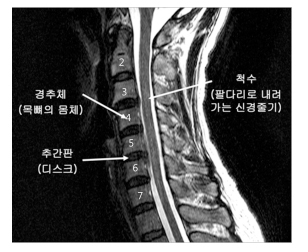

총 7개로 이루어진 목 뼈의 사이에 존재하고 있는 추간판을 다른 말로 디스크라고 합니다. 이 디스크는 뼈와 뼈 사이의 충격을 완화 시키고 안정성을 주는 역할을 합니다. 이러한 디스크가 잘못된 자세나 충격 등으로 인하여 제자리에서 점점 탈출하여 옆을 지나가는 신경을 누르면 우리가 흔히 일컫는 '목 디스크'라고 얘기합니다. 정식 명칭은 경추수핵탈출증입니다.

먼저 머리에서 가까운 쪽부터 1번에서 어깨쪽까지 총 7개의 뼈가 있는데요. 1번, 2번, 3번에서 나가는 신경은 어깨 밑으로 분포하지 않습니다. 따라서 1~2번 사이, 2~3번 사이, 3~4번 사이의 디스크에 문제가 발생 하는 경우라면 사람들이 흔히 말하는 디스크의 증상이 나타나지 않습니다. 하지만 머리와 가깝기 때문에 두통, 현기증, 가슴 답답함 등의 증상이 있을 수 있습니다.

문제는 아래쪽인데요. 아래쪽 경추의 신경근은 어깨, 팔, 손가락으로 이루어져 있습니다. 특히 목 디스크 환자의 90%가 4~7번 경추 사이에서 발생하기 때문에 아래쪽 디스크의 문제가 발생 했을 때 나타나는 증상을 대부분 겪는 것이지요. 4~7번 경추는 목 뼈의 움직임이 가장 크기 때문에 대부분의 목 디스크가 발생합니다.

위의 그림과 같이 문제가 생긴 경추에 따라 증상이 나타납니다.